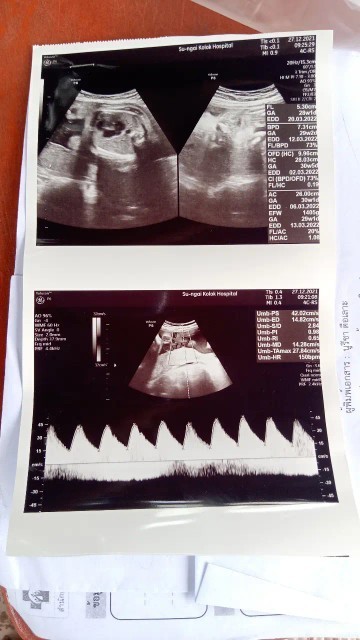

ยังงี้มองออกไหมคะ ว่าเพศอะไร

ช่วยดูหน่อยคะแม้ว่า บ้านนี้หญิงหรือชาย

โด่เด่ มาเหมือนผมเลยคับ ลูกชายค่าแม่

เห็นชัดเลยค่ะ ผู้ชายแน่นอนค่ะแม่

ชายล้าน%ของบ้านนี้เหมือนแม่เลยคะ

ไข่นำขนาดนั้นผู้ชายจ้า

ไข่ใหญ่มว๊ากกกกกกคะ.....คุณแม่😂

ไอ้จู๋100%ค่ะคุณเเม่. ไข่ชัดเเจ๋ว